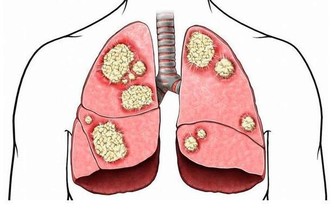

維生素C抗氧化效果明顯,有利於促進人體新陳代謝速度,抑制黑色素形成,幫助皮膚變得白皙。維生素C在治療敗血症方面還有重要作用。

如果人體缺乏維生素C,就會對健康帶來嚴重影響,包括敗血症、牙周出血、蛀牙、多汗、軟骨病等。

所以,平時也要注意攝取維生素C,即可以服用一些藥片,也可以多吃檸檬、獼猴桃、西紅柿等果蔬。